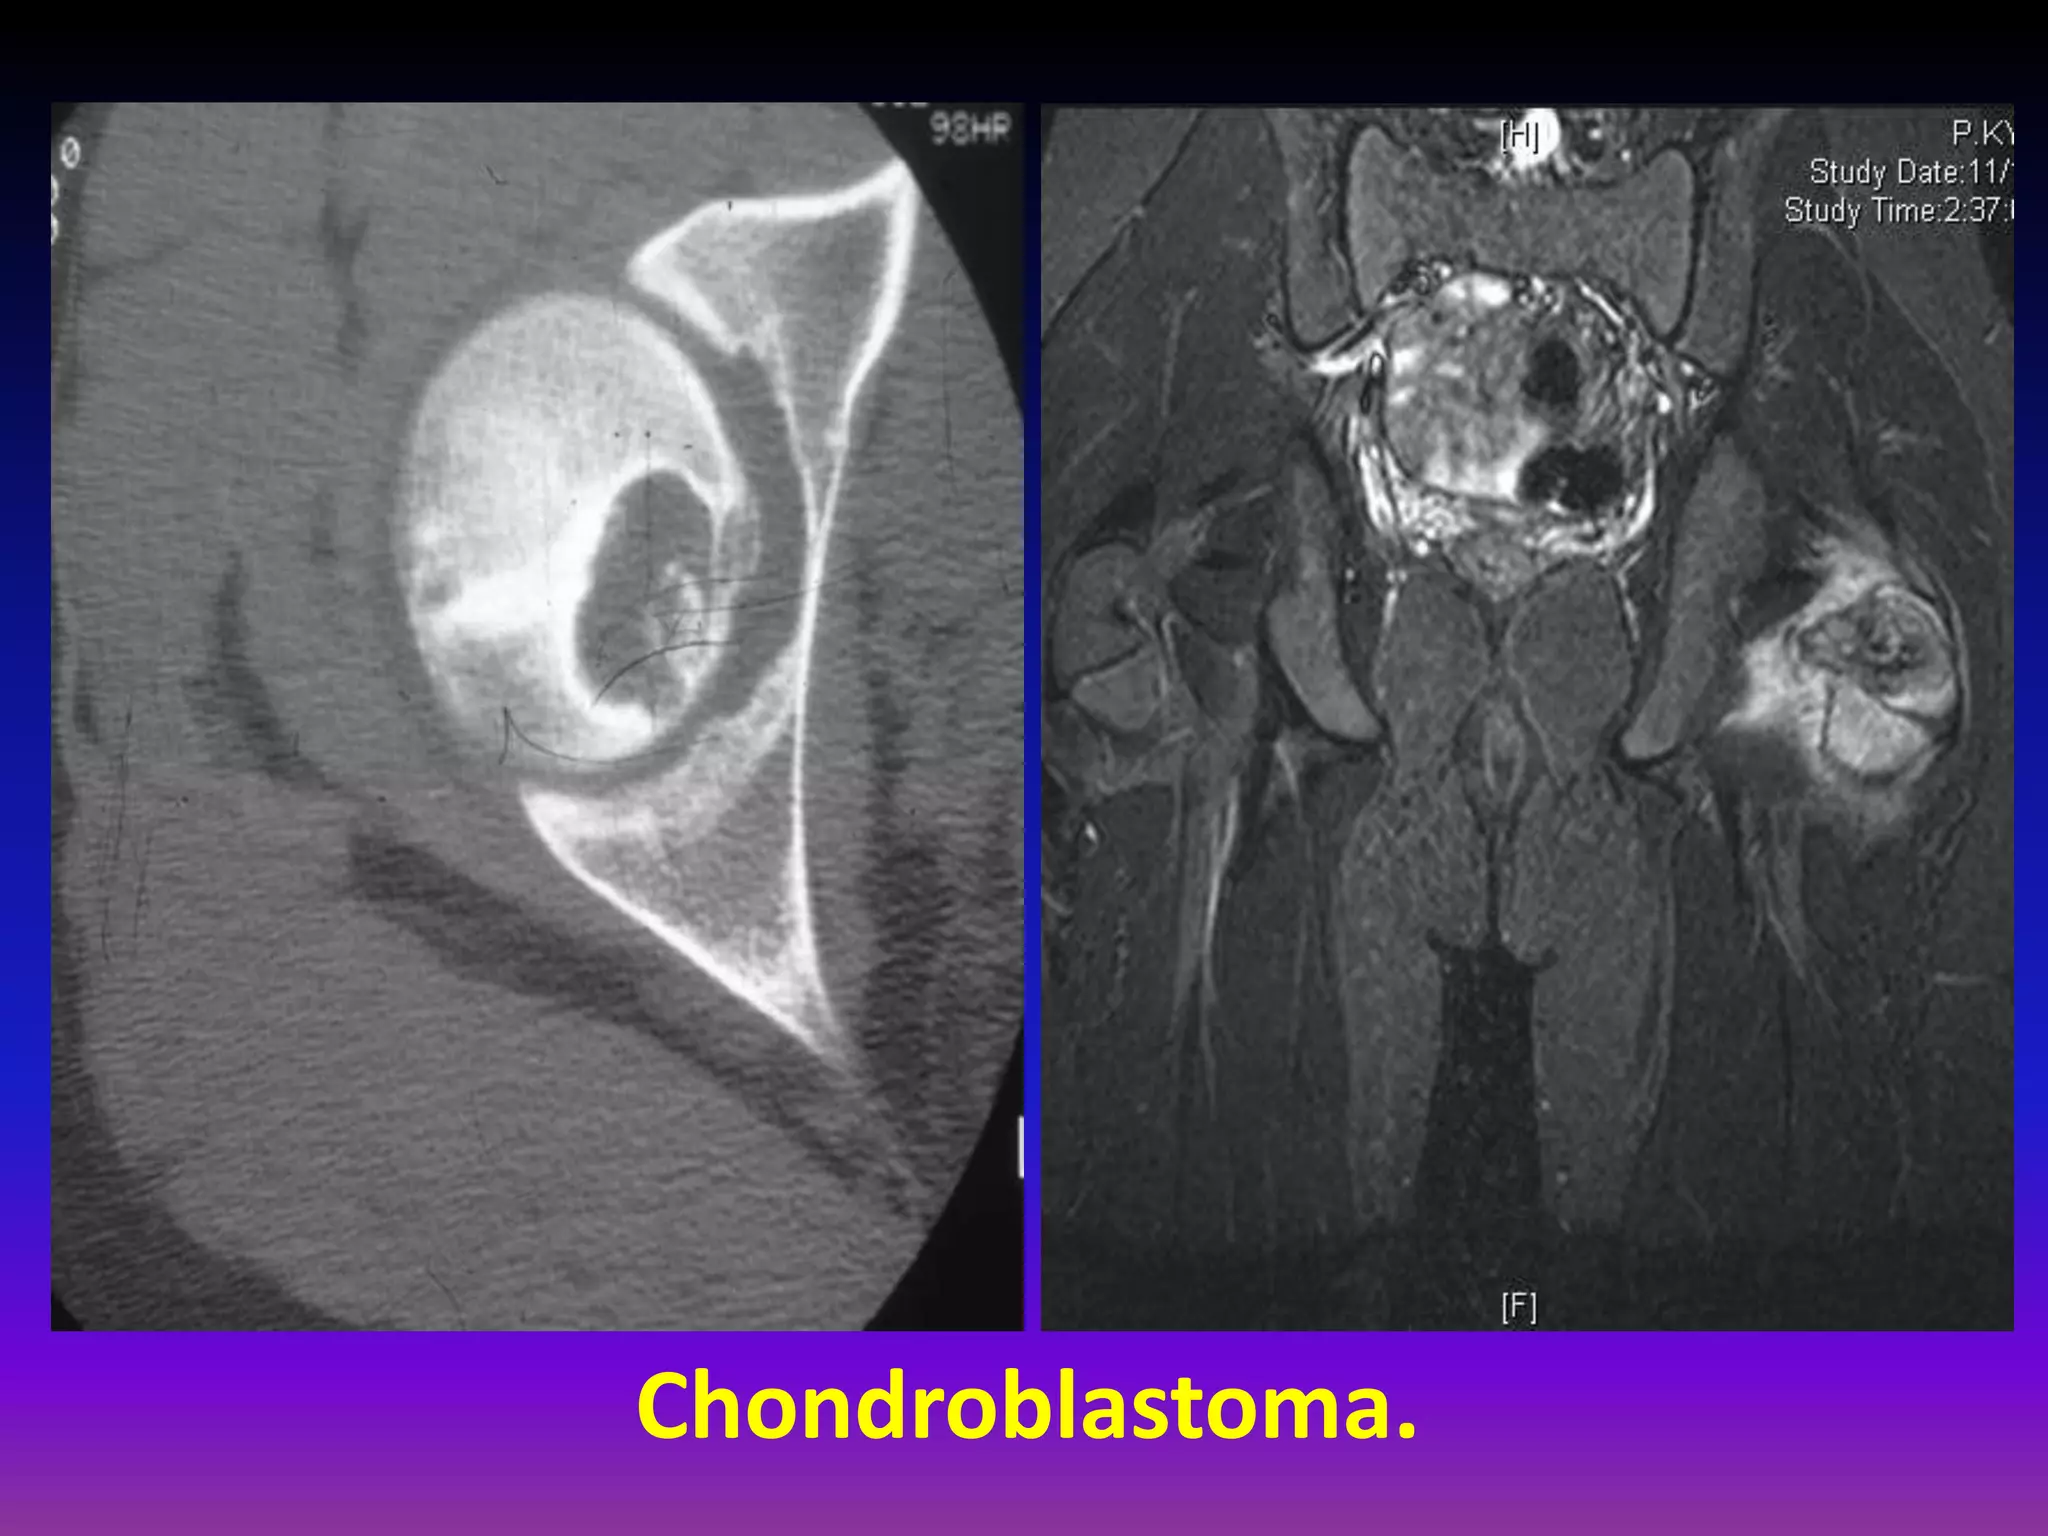

Chondroblastoma.

Rare, benign tumor derived from chondroblasts

(5% of benign bone tumors)

Epiphysis of long bones (also apophyseal

Most common sites

Femur, humerus, tibia

apophyseal) .

Male : female = 3 : 2

Mean age: skeletally immature

May have behavior not normally associated

with benign tumors (pulmonary metastases,

local bone / soft tissue invasion).

Clinical Presentation.

Pain near a joint without history of trauma

Tumor can induce a secondary synovitis

Patient may have a joint effusion

Pathological fracture rare.

Radiographic Appearance:

Lytic well-defined margins

Scalloping or erosion

of cortical bone may be present

Fine calcifications (punctate , rings).